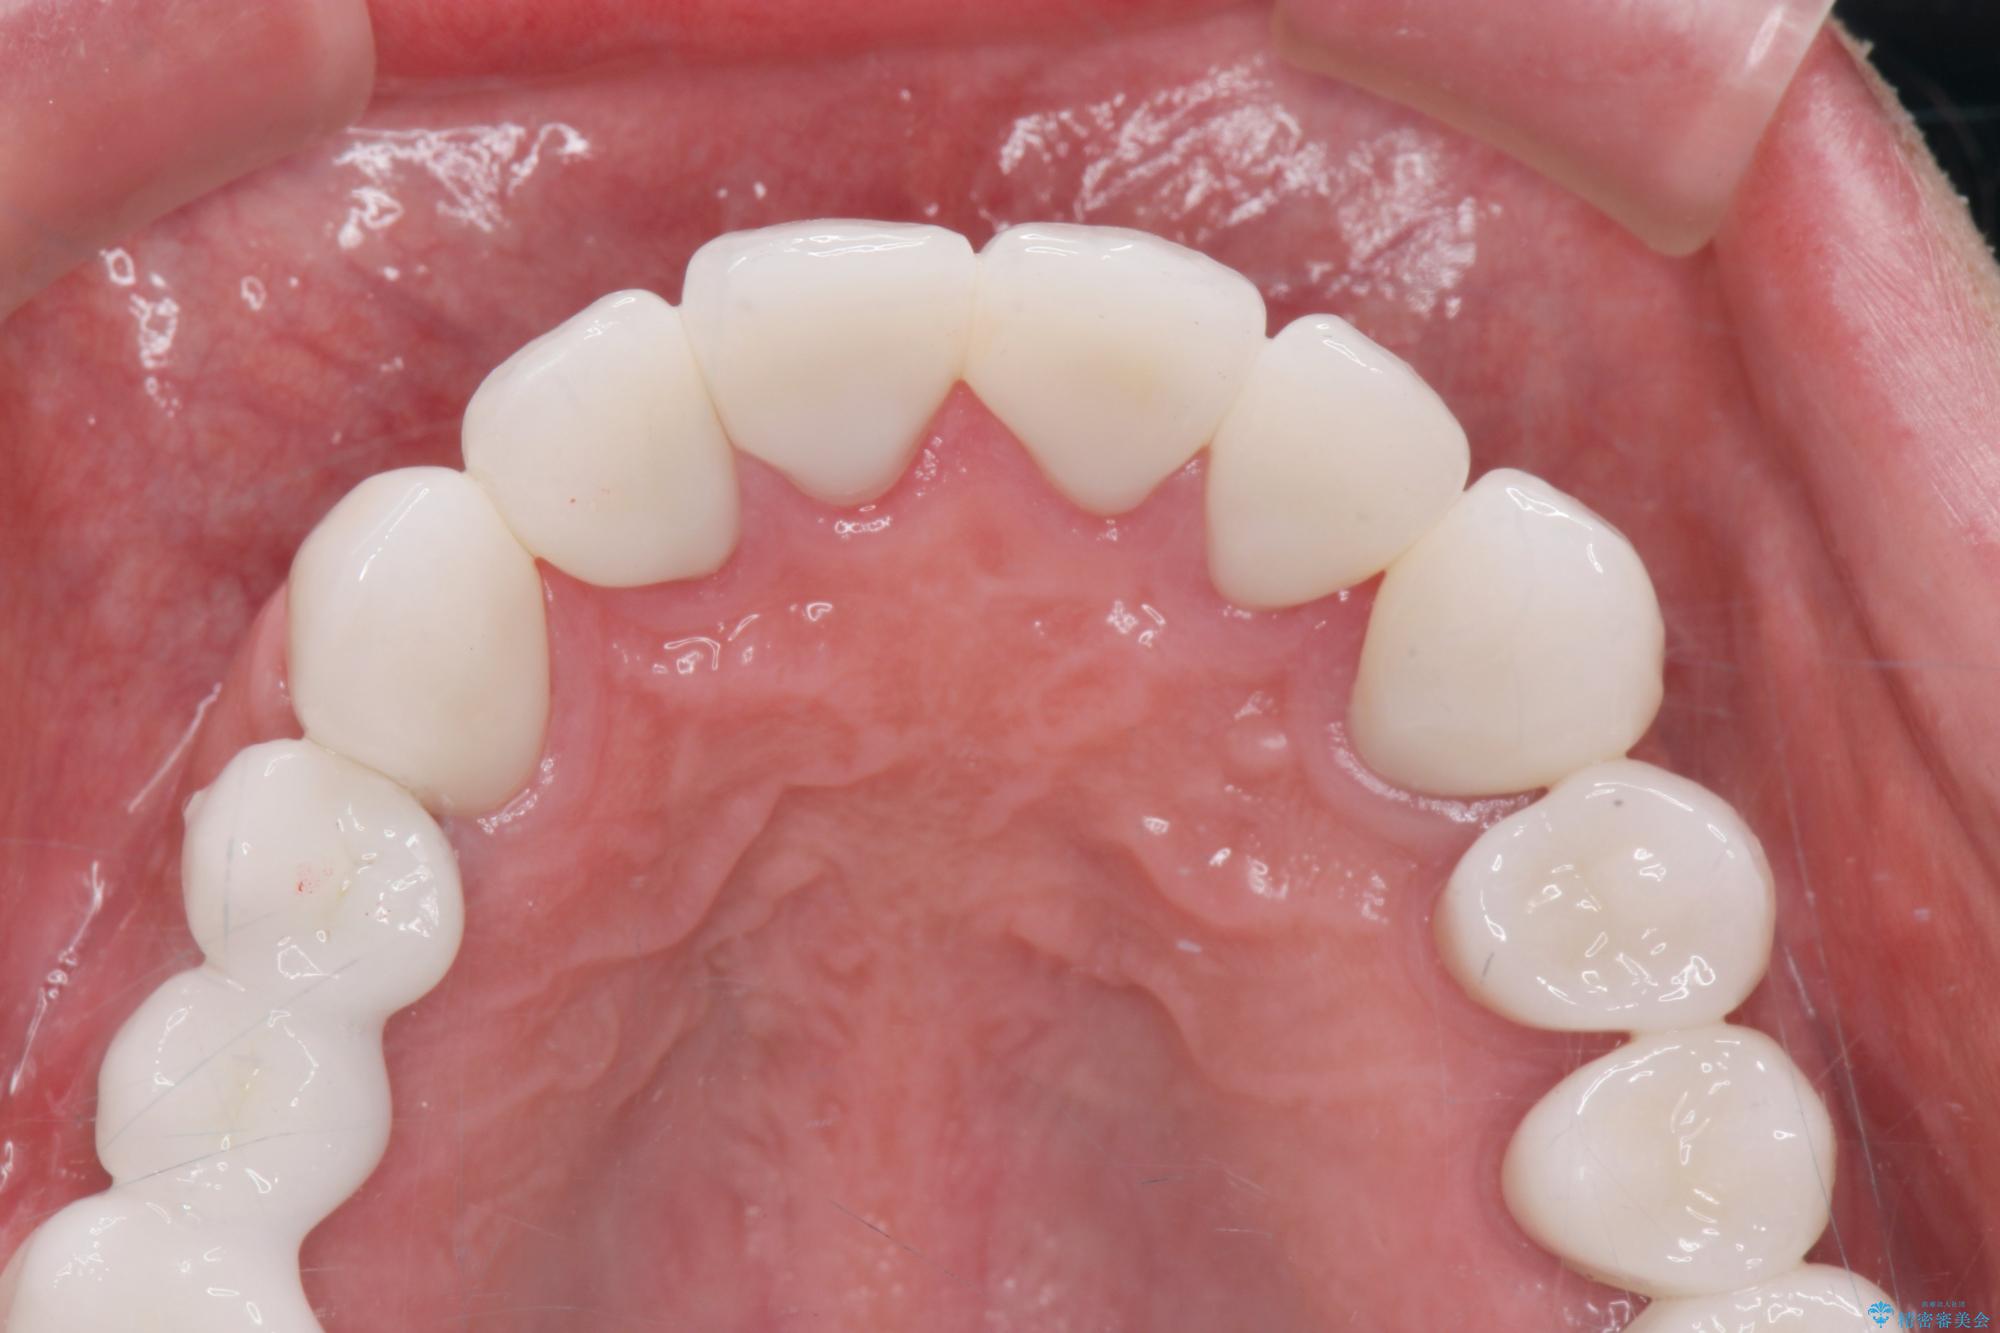

[ 歯周外科手術 ] セラミック治療後の歯ぐきの違和感

セラミッククラウンを除去し仮歯を装着し、歯周外科手術を行い歯ぐきの状態を改善したのち、適合の良いセラミッククラウンを再作製をする治療計画としました。

- 90.2万円(ジルコニアクラウン×6・仮歯×6 ・歯周外科手術)費用は治療当時の料金となります

見た目の良いクラウンが装着されていても、歯ぐきの状態が悪ければ違和感や歯ぐきの腫れ、臭いの元となっていることが多く見られます。